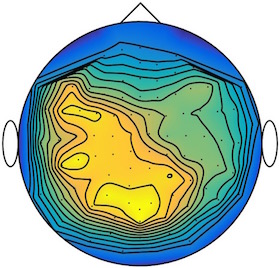

We applied our method to a magnetoencephalography (MEG) dataset. In this setup, brain activity of a subject is recorded (Elekta Neuromag, 306 sensors of which 204 planar gradiometers and 102 magnetometers, sampling frequency 1000Hz) while the subject reacted to the presentation of a target stimulus by pressing either the left or the right button.

Data is preprocessed applying signal space separation correction, interpolation of noisy sensors, and realignment of data into a subject-specific head position (MaxFilter, Elekta Neuromag). The signal was then filtered (low pass 40HZ), and artifacts such as blinks and heartbeats removed thanks to Signal-Space Projection using the Brainstorm software222http://neuroimage.usc.edu/brainstorm. The samples we used for our barycenter computations are an average of the norm of the two gradiometers for each channel from stimulation onto 50ms and the classes were left or right button.

| Class 1 | Class 2 | ||||||

|

|

|

|

|

|

|

|

| Sample 1 | Sample 2 | Sample 3 | Mean | Sample 1 | Sample 2 | Sample 3 | Mean |

|

|

|

|

|

|

|

|

This results in two classes of recordings, one for each pressed button. We aim at computing a representative activity map for each class using Wasserstein barycenters. For each class we have recordings each having samples located on the vertices of an hexahedral mesh of a hemisphere (corresponding to a MEG recording helmet). These recorded values are positive by construction, and we rescale them linearly to impose . Figure 6, top row, shows some samples from this dataset, displayed using interpolated colors as well as iso-level curves. The black dots represent the position of the electrodes on the half-sphere of the helmet, flattened on a 2-D disk.

We computed TV-regularized barycenters independently for each class by solving (16) with the TV regularization using the projected gradient descent method (22). We used a squared Euclidean metric (24) on the flattened hemisphere. Since the data is defined on an irregular graph, instead of (23), we use a graph-based discrete gradient. We denote the graph which connects neighboring electrodes. The gradient operator on the graph is

The total variation on this graph is then obtained by using , the norm, i.e. we use in (23).

Figure 6 compares the naive barycenters (i.e. the usual mean), barycenters obtained without regularization (i.e. ) and barycenters computed with an increasing regularization strength . The input histograms being very noisy, the use of regularization is important to make the area of significant activity emerge from the noise. The use of a TV regularization helps to keep a sharp transition between active and non-active regions.